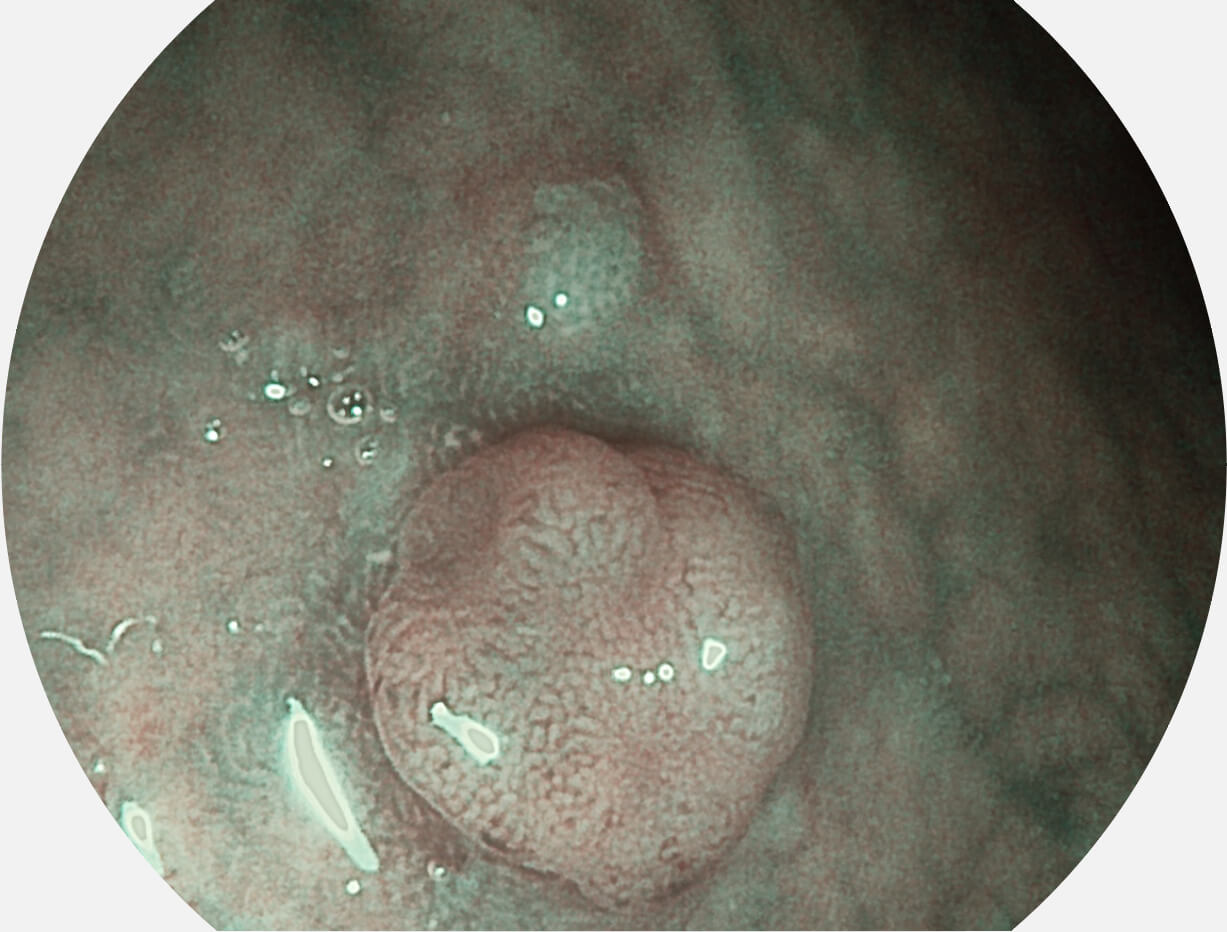

SFI图像

白光图像